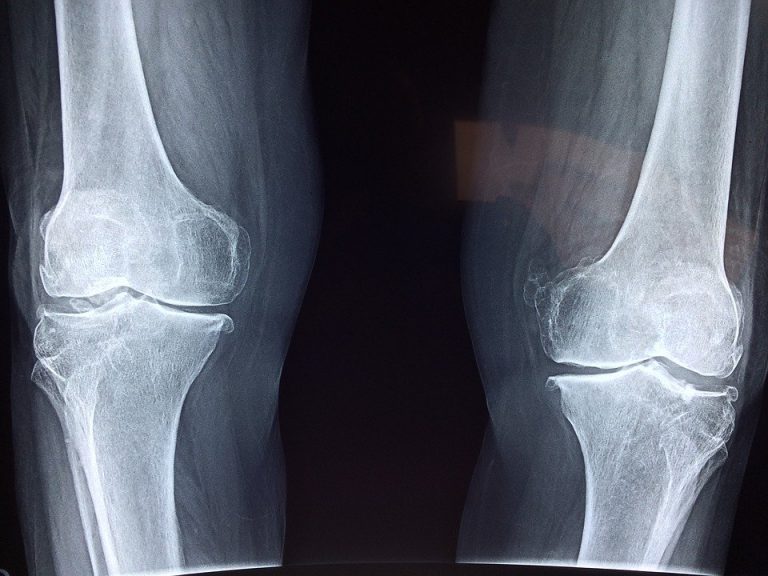

En général, l’IRM du genou est prescrite en deuxième intention après la radiographie ou l’échographie. Il permet d’obtenir des images plus précises ou de détecter des lésions qui n’ont pas été détectées par les examens d’imagerie précédents. L’IRM du genou est souvent utilisée pour détecter les blessures causées par un choc traumatique (par exemple, les accidents de voiture, les blessures sportives). Il est particulièrement utile comme outil de diagnostic en cas de rupture du ligament croisé, de luxation de la rotule ou encore de lésion du ménisque. Il est également utile pour les entorses du genou et les tendinites. Plus rarement, elle peut révéler la présence de tumeurs, bénignes ou non. Enfin, une IRM de l’articulation du genou peut être réalisée pour préparer au mieux l’intervention chirurgicale.